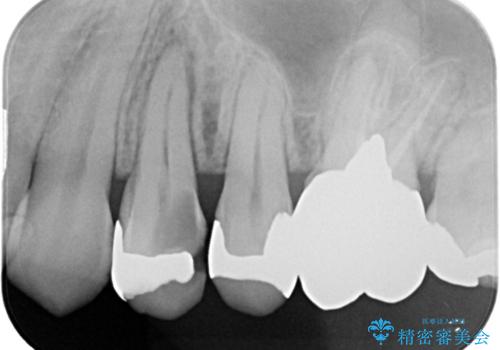

大きい虫歯 根管治療〜オールセラミッククラウン

- 大きな虫歯を認めた患者様です。

自発痛を認めたことから、不可逆性歯髄炎の診断を行い治療を介入しております。

根管治療した場合は速やかに被せ物による修復が必要です。